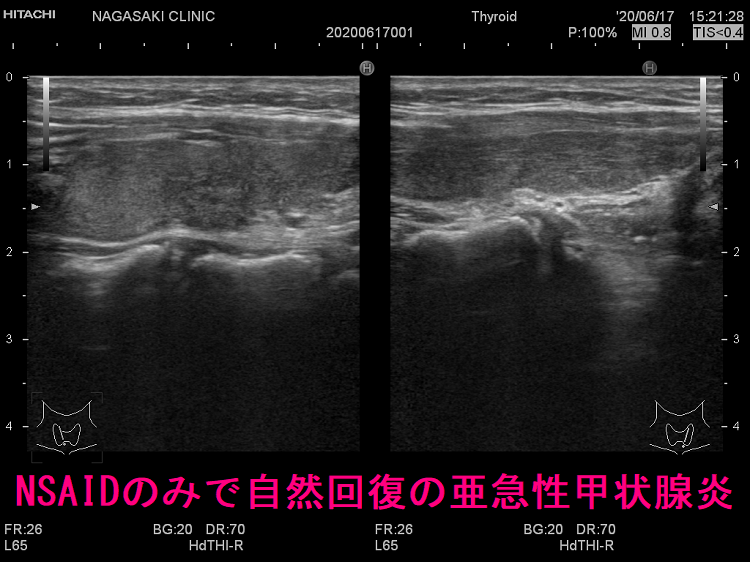

亜急性甲状腺炎の治療。副腎皮質ホルモン剤(ステロイド剤)が劇的に効き、2-3日で痛みは消え、熱も下がり治ったように錯覚。服薬中止で1週間以内に元に戻る。ステロイドを平均3-4か月掛けてゆっくり着実に減量。齲歯(虫歯)治療中、高齢者では使い難い。甲状腺機能亢進症/バセドウ病に使う抗甲状腺薬(メルカゾール、プロパジール、チウラジール)は無効。ロキソニンなどの非ステロイド系抗炎症剤(NSAIDs)は対症療法で、亜急性甲状腺炎自体の炎症を抑えない。ステロイドの副作用、高齢、齲歯(虫歯)治療中、自然治癒する可能性などの理由で使用。

亜急性甲状腺炎には副腎皮質ホルモン剤(ステロイド剤)が劇的に効きます。たいてい服薬開始後2-3日で痛みも消え、熱も下がり、治ったような錯覚に陥ります。これにだまされ、服薬中止すれば(患者の自己判断・治療経験のない医者)、1週間以内に元の症状に戻り、最初から副腎皮質ホルモン剤(ステロイド剤)投与をやり直さねばなりません。最善の方法は、エコー所見が改善しているか確認しながら副腎皮質ホルモン剤(ステロイド剤)をゆっくり着実に減量するやり方です。(平均3-4か月は掛かります。)

ロキソニンなどの抗炎症薬(NSAIDs)は、痛みを和らげる・熱を下げる対症療法で、亜急性甲状腺炎自体の炎症を抑えません。抗炎症薬を使用するのは、

- 非常に軽度の亜急性甲状腺炎で、副腎皮質ホルモン剤(ステロイド剤)を投与しなくても自然治癒する可能性が高い